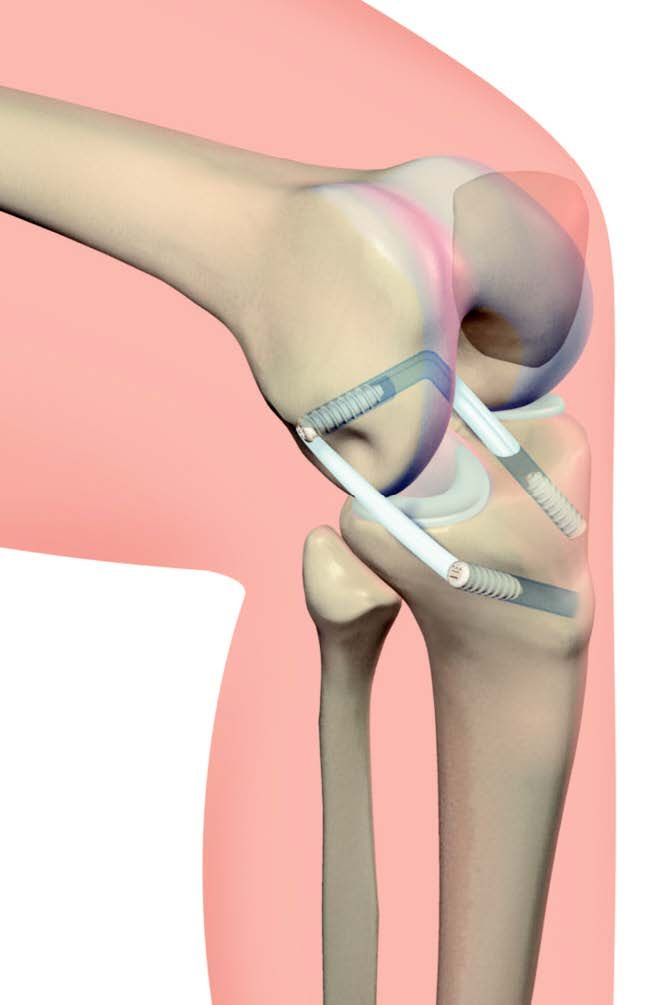

Reprise de prothèse unicompartimentale par prothèse totale de genou. Technique assistée par ordinateur.